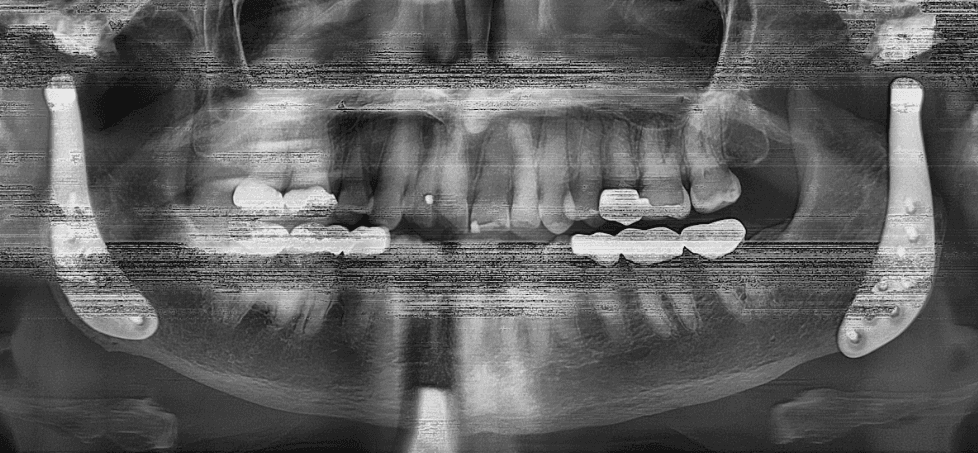

X-RAYS